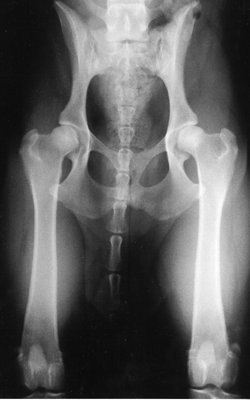

The PennHIP method is a novel way to assess, measure and interpret hip joint laxity. It consists of three separate radiographs: the distraction view, thecompression view and the hip-extended view. The distraction view and compression view are used to obtain accurate and precise measurements of joint laxity and congruity. The hip-extended view is used to obtain supplementary information regarding the existence of osteoarthritis (OA) of the hip joint. (The hip-extended view is the conventional radiographic view used to evaluate the integrity of the canine hip joint.) The PennHIP technique is more accurate than the current standard, and it has been shown to be a better predictor for the onset of OA.

The radiographs pictured here are of the same dog, yet the hip joint laxities in each view look very different. Notice that the hips in the distraction view appear to be much looser than they do in the hip-extended view.

Distraction View Compression View Hip-Extended View

The looser the joint on the distraction view, the greater is the chance that the hip will develop OA. The hip-extended view tends to mask true hip joint laxity because the joint capsule is wound up into a tightened orientation when the hips are extended. This explains why measurable joint laxity on the distraction view is always greater than the measurable laxity from the hip-extended view. In fact, distraction laxity is up to 11 times greater depending on the breed of dog under study.